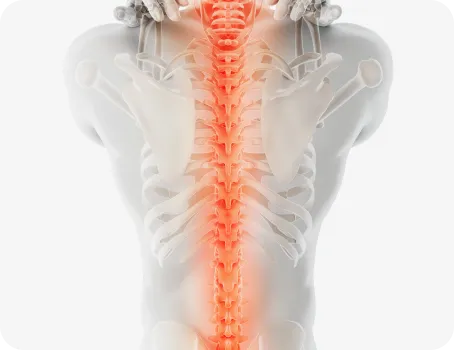

척추

척추측만증 또는 좌, 우 한쪽으로 기울어진 척추로 인해 체중이 한쪽 허리로 집중된다면 장기적으로 체중이 기울어진 쪽 허리에 뼈가 자라거나 퇴행성 변화가 빠르게 진행됩니다.